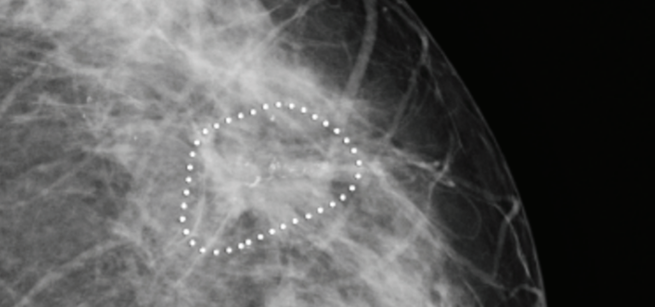

Illustration of suspicious microcalcification clusters using iCAD software on cranio-caudal views of a 74 years old woman with a lump in the right breast. iCAD software identified microcalcification clusters with suspicious morphology (iCAD Inc. Caption